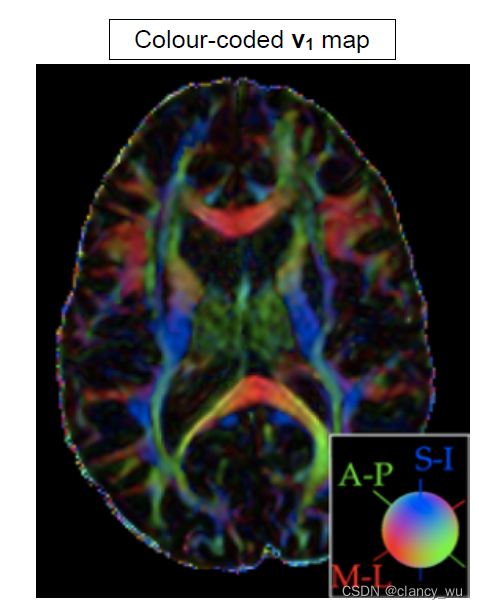

下面是常见的纤维束方向估计图: